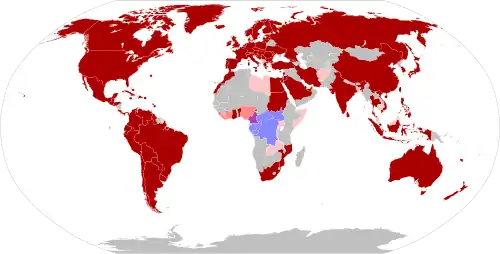

| Location | 121 countries and territories (119 with confirmed cases, 2 with suspected cases only) |

In May 2022, the World Health Organization (WHO) made an emergency announcement of the existence of a multi-country outbreak of mpox, a viral disease then commonly known as "monkeypox".[7] The initial cluster of cases was found in the United Kingdom,[8] where the first case was detected in London on 6 May 2022[9] in a patient with a recent travel history from Nigeria where the disease has been endemic.[10] On 16 May, the UK Health Security Agency (UKHSA) confirmed four new cases with no link to travel to a country where mpox is endemic.[9] Subsequently, cases have been reported from many countries and regions.[11] The outbreak marked the first time mpox had spread widely outside Central and West Africa. The disease had been circulating and evolving in human hosts over several years before the outbreak and was caused by the clade IIb variant of the virus.[12]

On 23 July 2022, the Director-General of the WHO, Tedros Adhanom Ghebreyesus, declared the outbreak a public health emergency of international concern (PHEIC), stating that "we have an outbreak that has spread around the world rapidly, through new modes of transmission, about which we understand too little".[13] A global response to the outbreak included public awareness campaigns in order to reduce spread of the disease, and repurposing of smallpox vaccines.[14][15]

In May 2023, the World Health Organization declared an end to the PHEIC, citing steady progress in controlling the spread of the disease.[16] Relatively low levels of cases continued to occur, and as of 30 June 2025, there have been a total of 150,889 confirmed cases and 377 deaths in 137 countries.[17][18][19]